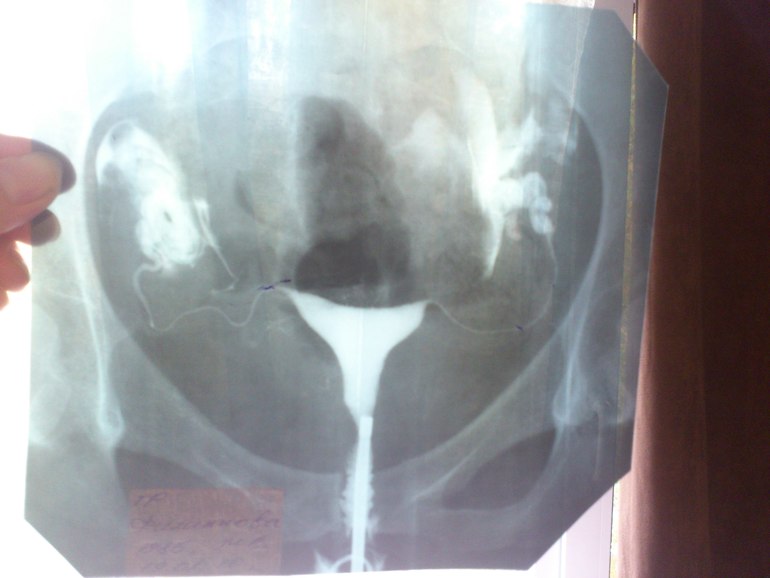

слева не оч...((а так...сказать что все запущено - нельзя.только по снимку ведь нельзя делать окончательные выводы.[removed](function () {

вот мой снимок 4 года назад делала примерно! что-то не грузится

Это снимок проходимости труб, мне такой делали. Мне кажется матку раствор заполнил, а труб не видно. Если быраствор заполнил трубы они бы тоже белого цвета были как и матка, но может на фото не видно,т.к. они тоненькие

правой трубы не видно видно как она увеличенна ....а левая действительно тоненькая но ее видно просто она витая и припаялась к матке (так мне врач объяснял , который делал), но жидкость то вышла вся в полость и снимок один делали...сестра гинеколог(не знаток в ГСГ)говорит что если жидкость вышла в полость значит все хорошо и еще одна врачица так же говорит....